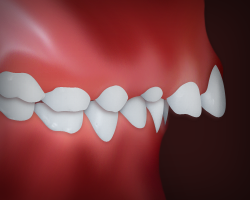

Crowding